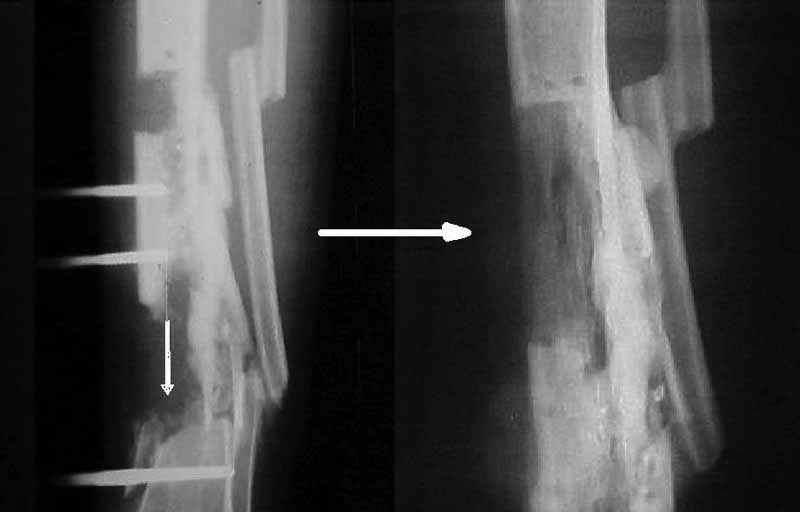

Я бы сделал пластику мягких тканей (торакодорзальный лоскут совместно с микрохирургами или пластику латеральной головкой икроножной мышцы) и выполнил бы краевой отщеп большеберцовой кости для его дистракции аппаратом в проксимальном направлении (рис. 1 – пример применения отщепа (авторство не мое), рис. 2 – схема предлагаемого варианта замещения дефекта кости).